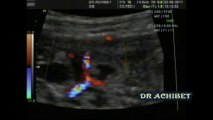

Dissection de l'aorte

Dédoublement de la paroi aortique chez un

Homme de 60 ans

Grand tabagique